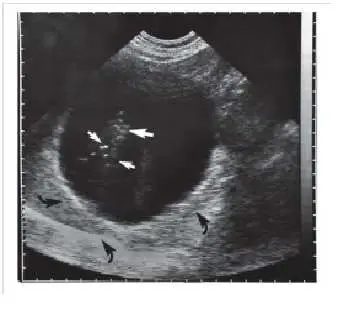

超音波影像顯示一顆腎臟的橫切面。影像中可見:

- 白色箭頭:指向腎臟實質內的數個高回音亮點(hyperechoic foci),排列於腎竇附近,呈現強烈反射訊號,提示強反射界面的存在(如腎結石、鈣化或腎盂黏膜反射)。

- 黑色箭頭(影像下方):指向強反射體後方的聲影(acoustic shadowing),這是超音波遇到強反射或強衰減界面時,後方因能量耗盡而產生的低回音暗帶,屬於確定性假影,在腎結石診斷中具有重要臨床價值。

在彩色都卜勒或脈衝波都卜勒(pulsed wave Doppler)模式下,若 PRF 設定不當(偏低),高速血流的都卜勒頻移將超過 Nyquist 極限(= PRF/2),形成混疊假影,表現為血流方向錯誤或頻譜「折返(wrap-around)」。本題的影像脈絡指向都卜勒模式下的混疊相關假影。